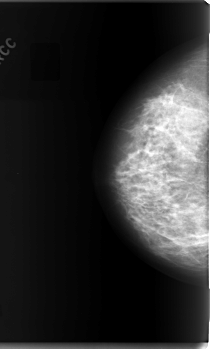

C_0070_1.LEFT_CC

LEFT_CC LINES 5960 PIXELS_PER_LINE 3576 BITS_PER_PIXEL 12 RESOLUTION 50 OVERLAY

FILE: C_0070_1.LEFT_CC.OVERLAY

TOTAL_ABNORMALITIES 1

ABNORMALITY 1

LESION_TYPE MASS SHAPE IRREGULAR MARGINS ILL_DEFINED

ASSESSMENT 4

SUBTLETY 3

PATHOLOGY MALIGNANT

TOTAL_OUTLINES 1

BOUNDARY